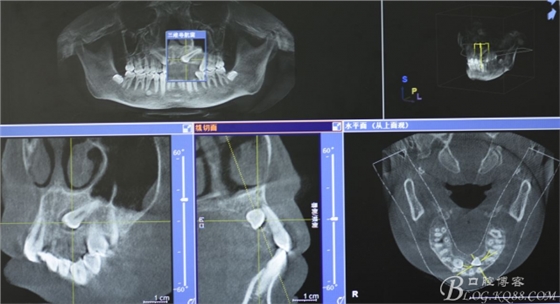

圖1.右側(cè)上頜13cbct檢查:牙冠位于腭側(cè)、牙根接近上頜竇

圖2.cbct檢查:23牙冠位于腭側(cè),提示開窗的手術(shù)近路選擇在腭側(cè)